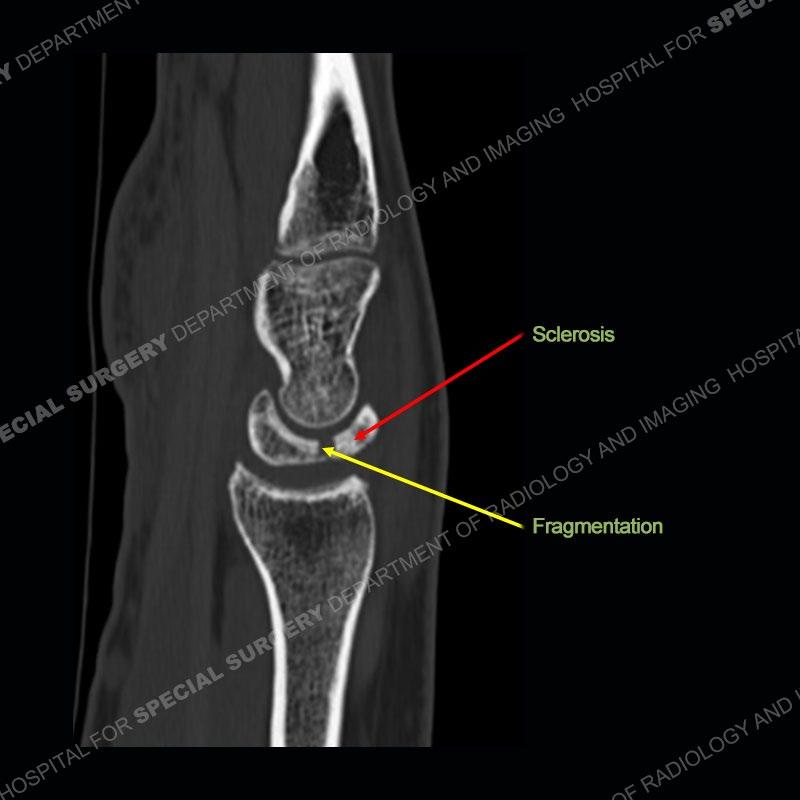

Both cases demonstrate similar findings to slightly less and more conspicuous degrees. The radiographs show sclerosis and fragmentation/collapse of the lunate. The CT images for case one just further clarify the architecture of the lunate. The MRI images show a slightly greater degree of variability but with overall persistent areas of low signal of the lunate on all pulse sequences and with a loss of the geometry of the lunate indicating collapse and fragmentation.

A well recognized but still poorly understood entity with necrosis and collapse representing the end stage of the pathology. The reasons for the necrosis are likely multifactorial and relate to the anatomy of the wrist inclusive of ulnar variance and the anatomy of the vasculature to the lunate. Other inflammatory, biological processes and overuse/trauma also likely play a role in the development of the necrosis. The disease manifests by sclerosis of the lunate followed by collapse and fragmentation. This is then followed by abnormal orientation of the scaphoid in a palmar flexed position and then adjacent arthritis. These latter processes were not the focus of this case presentation. The MRI will show areas of low signal on all pulse sequences indicating the areas of devitalized bone. The foci of slightly increased signal are in keeping with areas of maintained perfusion and highlight the variable architecture and findings of Kienbock’s. The fragmentation and collapse of the bone are seen well on both CT and MRI.